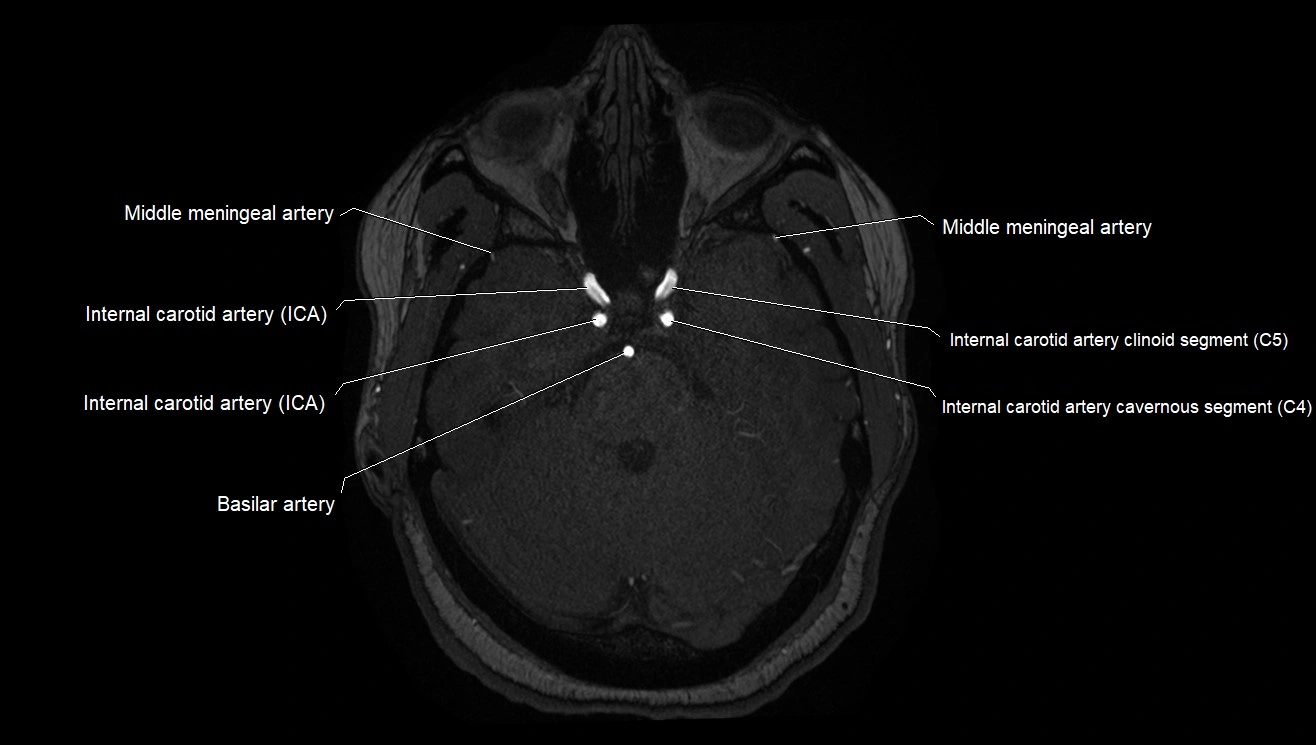

MRA (Magnetic Resonance Angiography):

• Flow-related enhancement makes the AChA appear as a bright, linear vascular signal against suppressed background

• High sensitivity for origin and proximal course; distal branches may be too small to resolve

• Detects stenosis, occlusion, aneurysm, AVM feeders

MRI images

image